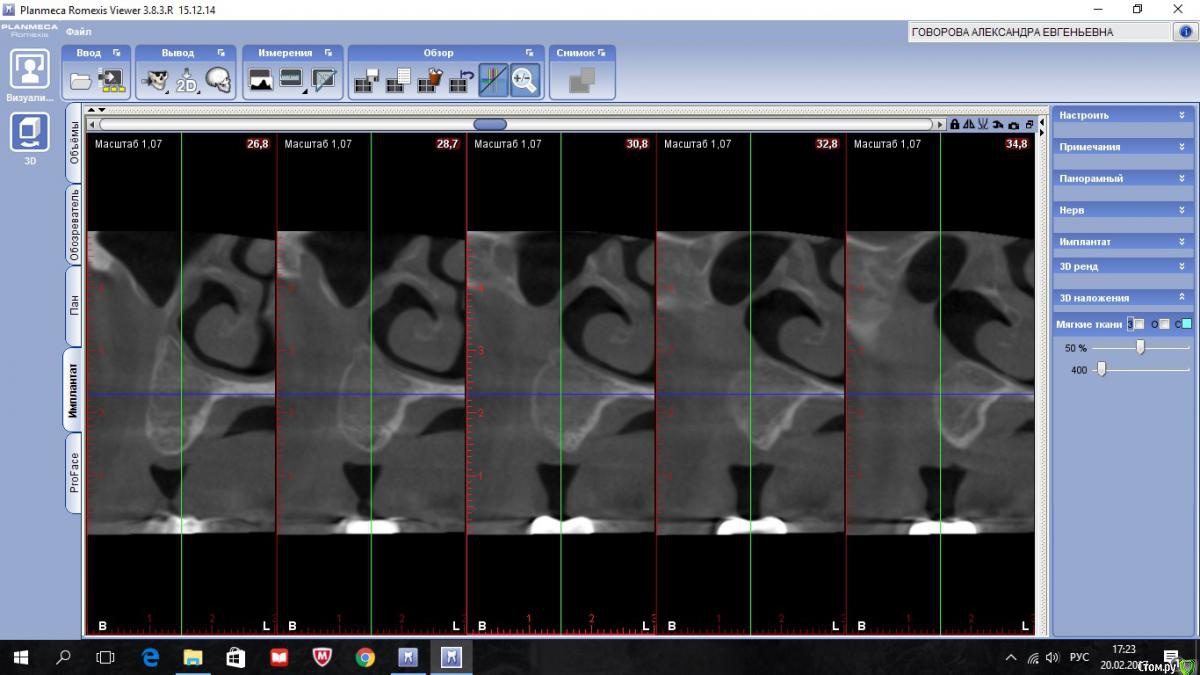

kriokov Опубликовано 20 февраля, 2017 Автор Поделиться Опубликовано 20 февраля, 2017 А разве Колдуэлл-Люк тут сильно виноват?не знаю, смотря что кто видит на снимках. Изначально--клиники синусита не было, смотрел пациентку на предмет иплантации во 2 сегменте, увидел рентгенологически тень с куполом в пазухе слева, 26 был живой на тот момент, отправил к лорикам, лорики в чло, кафедральные посмотрели- отпунктировали, вроде как получили кистозное наше содержимое. Соперировали.Посмотрел ее через месяц после гайморотомии. Нос дышал, чувствительность выпала, парус во рту по своду, но не критично. Решил подождать 6 мес.И вот сейчас картина -- клиники гайморита нет, дышит. Чувствительности нет, не восстановилась. По своду понятно- все как было. А вот рентгенологически картинка интересная-- там где не закрывалось латеральное окно, мягкие ткани туда и ввалились (наверное что на подобие рубцовых тканей), киста судя по всему была, как раз почти по верхней границе купола идет рост новообразованной кости. Кость по высоте 10-12 мм в обл 24 , 25, 26. Кто виноват (Колдуэлл или Пушкин) мне по барабану, я не эксперт, и не кафедральный. Думаю, если бы была возможность латеральное окно сеткой или мембраной перекрыть, пролапса мягких тканей внутрь не было бы. Ну и из разряда экзотики-- можно и на одном столе отработать члх и лорику. ИМХО 2 Ссылка на комментарий

kriokov Опубликовано 22 февраля, 2017 Автор Поделиться Опубликовано 22 февраля, 2017 вопрос основной как работать дальше с пациенткой. 1. носовое дыхание свободное2. естественное соустье работает, дырка в нижнем носовом тоже не заросла3. лор посмотрел -- дал заключение, что это не та патология, которую ЛОРики пользуют4. болты вкрутить- не вопрос, как понимаетеЧего делать с дырой?Варианты -- 1. соперировать, -- убрать мягкие ткани аккуратно из пазухи, поставить или фольгу или сетку-- окно то закрою конечно, заоодно гляну чего с подглазничным, на кт отверстия не видать , или снесено, или просто не визуализируется. НО , но, но- останется имеющаяся контрапертура в нижний носовой. Через год , полтора, может появиться симптоматика , как у пациентов после радикальной2. не трогать ничего, поставить болты.Буду говорить с пациенткой Ссылка на комментарий